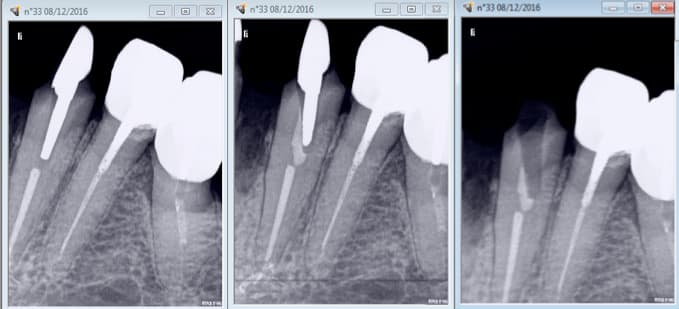

Bridge 41 31 32 33.....

Gouré de ciment de scellement. Utilisé du luxacore à la place. Impossible de sceller inlay core de 33 c'était pris. -)

Bon on ne va pas essayer de faire un tenon plus long et virer le reste de luxa core. . -)

La radio c'est à quel moment? Après ou avant d'avoir essayé de virer le luxacore?

A priori t'es pas dans l'axe..... parti de travers en essayant d'éliminer le mauvais ciment?

J'essaierai fraise boule acier col long petit diametre sur contre angle bleu ou vert pour creuser dans le residu au fond, retrouver la lumiere canalaire et essayer de recuperer l'axe pour refaire i core.

Et sinon, pas possible de coller un tenon titane et faire une reconstitution collée SC33? (je sais t'aimes pas mais des fois ça peut rendre service).

Sachant que tu as d'autres piliers voisins solidarisables....